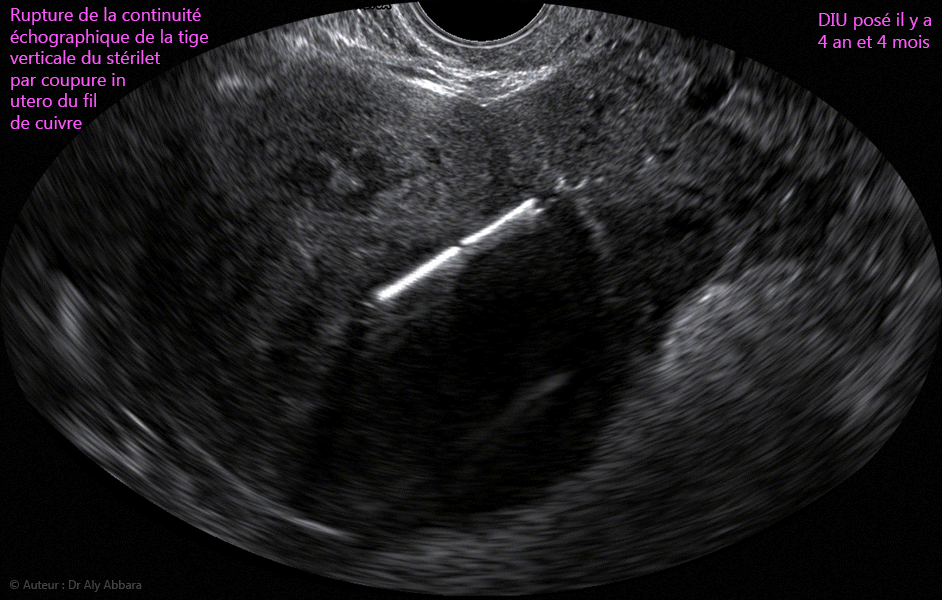

Images échographiques et séquence vidéo montrant, sur des coupes sagittales de l'utérus, la rupture de la continuité échographique de la tige verticale d’un DIU par coupure, in utero, de son fil de cuivre

• Il s'agit d'un dispositif in utero (DIU ou stérilet) posé dans la cavité utérine il y a 4 ans et 4 mois ; on peut supposer que l'origine de l'amincissement puis la fragilisation et enfin la coupure in utero du fil de cuivre sont dues à la libération en continu, durant toute cette période, du cuivre contenu dans ce fil enroulant la tige verticale du DIU.